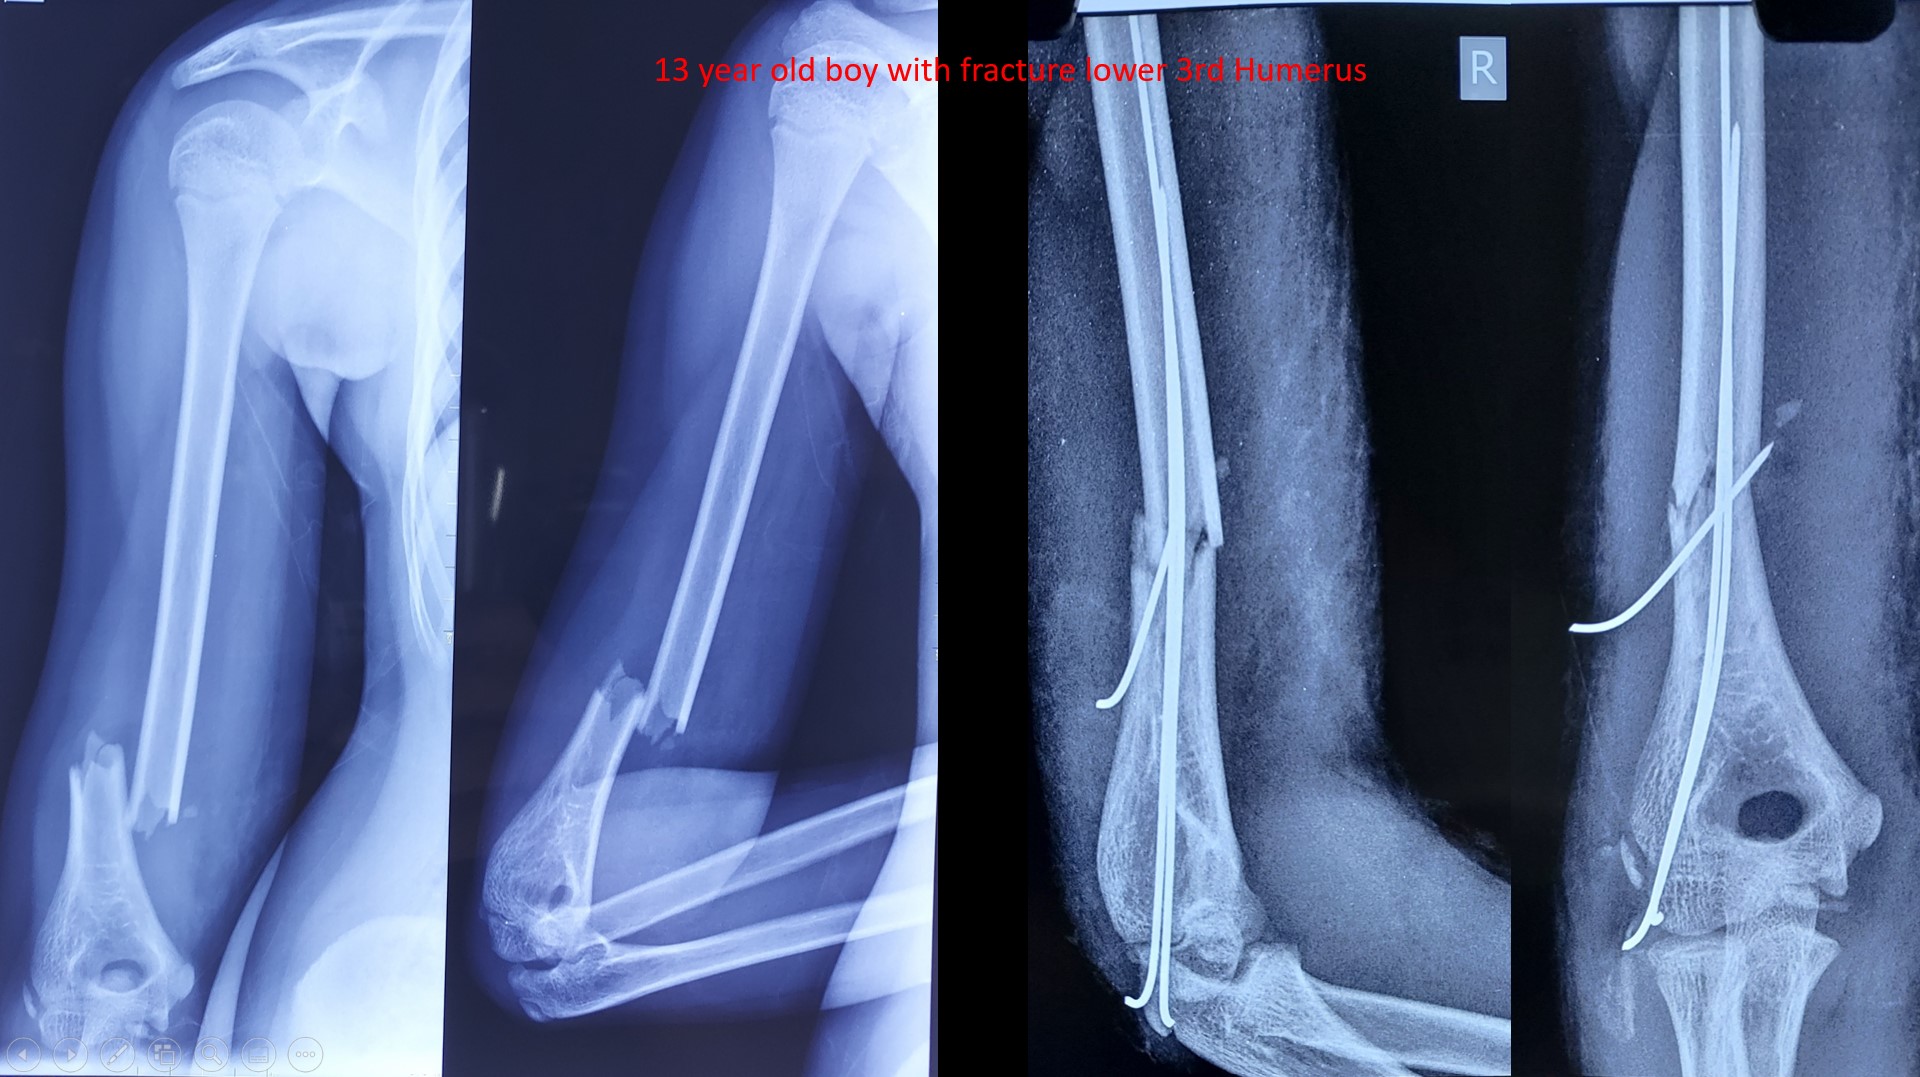

fRACTURE L3RD HUMERUS